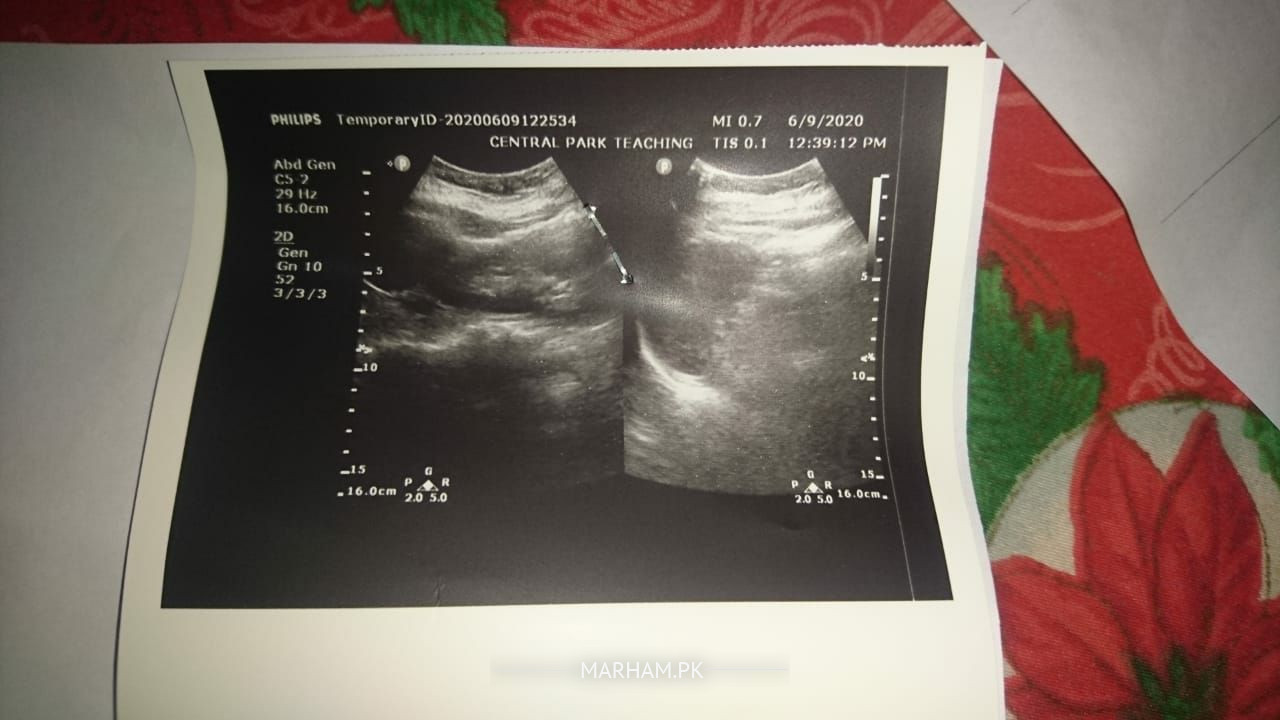

this abdominal ultrasound shows 3 stones in gallbladder..

rest of the report is fine..

Hie..!! this ultrasound report shows gall bladder stones.. what symptoms she's having currently??

Patient have gall bladder stone(pittay ki pathari)

stone in gall bladder

you are having cholilithiasis. yani pittay mai pathri hai.

the stone size is 21 mm which is considerably large and can cause blockage of duct as well.